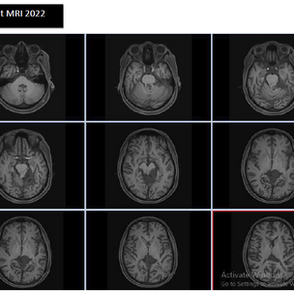

By December 2025, PET-CT imaging showed a clear and significant treatment response for my resolution of TNBC Ki-67 of 90%:

– Liver metastases had markedly reduced in size and metabolic activity

– Bone lesions were less active

– Lung nodules showed improvement

– The ulcerated breast tumour had become significantly smaller

This gave me a lot of hope. It confirmed what I do is heading to the right direction.